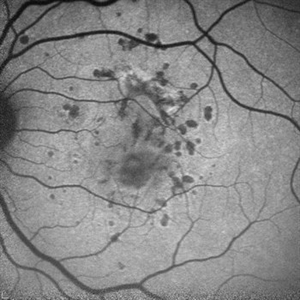

ToxocaraGgranuloma

Arterial phase fluorescein angiography of the patient with toxocara granuloma shows hypofluorescence in most part of the lesion and arterial supply to the lesion #2.